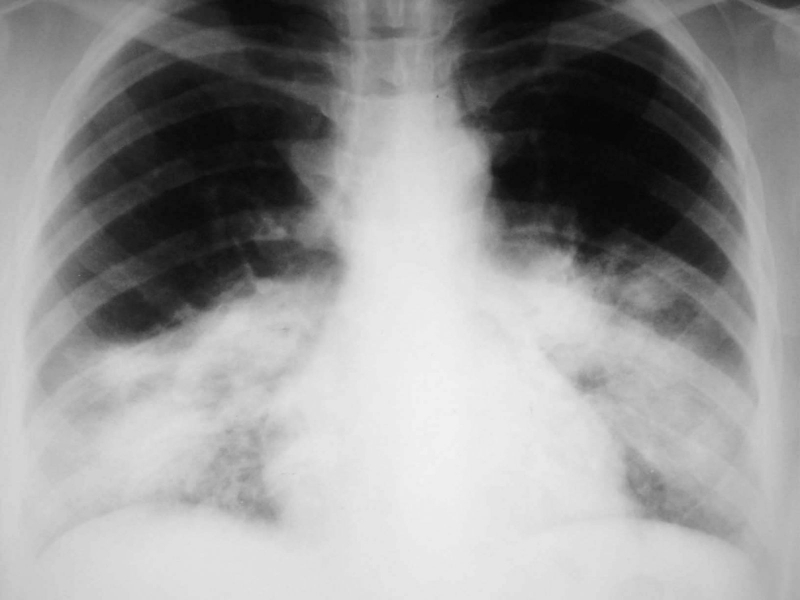

• Chụp X - quang, chụp CT cắt lớp qua chẩn đoán hình ảnh để kiểm tra bệnh nhân có tình trạng nhiễm trùng phổi hoặc bị dị tật xoang hay không.

Hội chứng Young: Nguyên nhân, triệu chứng, chẩn đoán và phương pháp điều trị 3 Chụp X - quang phổi là một trong các biện pháp giúp chẩn đoán hội chứng Young